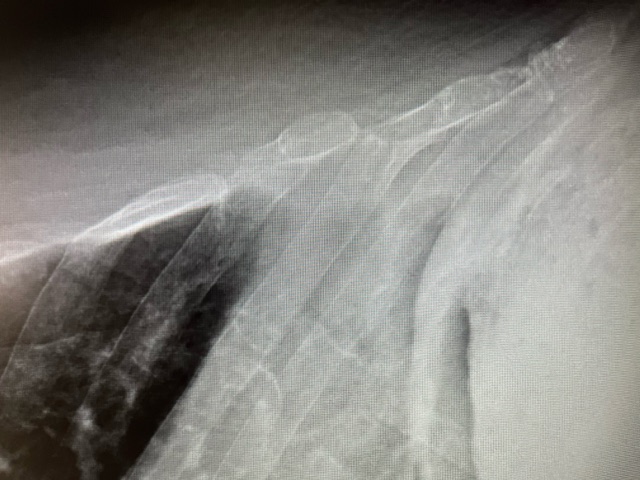

Posteriormente, se solicitó una radiografía de parrilla costal de carácter urgente que confirmó dichos hallazgos.

Por lo tanto, se trata de un caso de una fractura costal de 7-8º arco costal izquierdo tras caída casual.